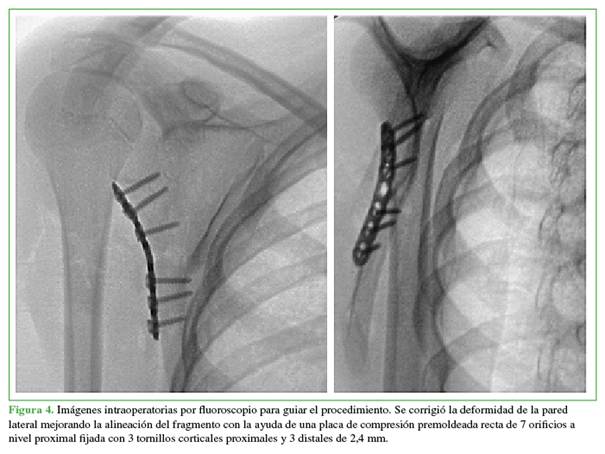

Se liberaron los fragmentos debido al abundante callo óseo con signos de consolidación a fin de mejorar la movilidad del fragmento en el foco de fractura y así recuperar la longitud de borde lateral de la escápula. La reducción se efectuó con pinzas reductoras y fijación provisional con clavos de Kirschner para alinear los fragmentos superior e inferior, y, en conjunto, lograr corregir el ángulo de la pared lateral, fijándola con la placa premoldeada en la región proximal y con tornillos corticales en el borde lateral (Figura 4).

La alineación, la reducción y la ubicación del material de osteosíntesis se confirmaron con el intensificador de imágenes. Se logró una adecuada angulación de cada tornillo sin disposición intrarticular. Se cerró la herida por planos y se evaluó de inmediato la movilidad del hombro. Los arcos de movilidad pasiva y activa asistida habían mejorado considerablemente. La paciente continuó usando un cabestrillo hasta el control posoperatorio.